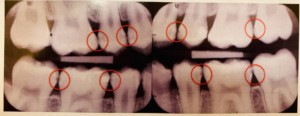

歯と歯の間のむし歯はなかなか判断が難しく、視診のみではX線を併用さした場合の50%以下しか隣接面のむし歯を検出できません。

佐賀市の歯医者、当院こども歯科医院ではX線の咬翼法により隣接面むし歯を検出しています。

これにより象牙質に至るむし歯の90%以上が検出されます。